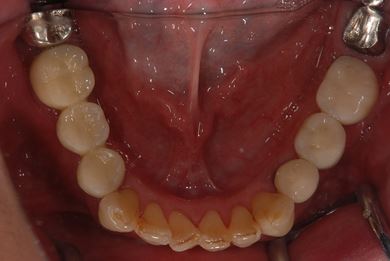

| カテゴリー | 【インプラント治療】【セラミック治療】 | ||||||||||||||||||||||||||||||||

| 性別/年齢 | 女性 / 40歳 | ||||||||||||||||||||||||||||||||

| 治療方針 | 右下奥、骨再生法によりインプラント治療を可能にする。 | ||||||||||||||||||||||||||||||||

| 治療内容 | インプラント3本(GBR、テンポラリーインプラント+仮歯)、ハイブリッドセラミックブリッジ3本、ハイブリッドセラミッククラウン2本 | ||||||||||||||||||||||||||||||||

| 総治療費 | 1,524,338円 | ||||||||||||||||||||||||||||||||

| 治療期間 | 1年0ヶ月 |